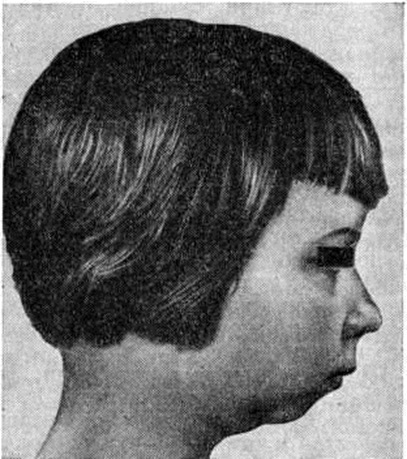

Характерными чертами ювенильного Ревматоидный артрит являются замедление физического развития, отставание в росте, а также нарушения роста отдельных сегментов скелета в связи с поражением близлежащих суставов, напр, недоразвитие нижней челюсти — микрогения (рисунок 10), укорочение или удлинение фаланг пальцев или других костей.

Рис. 10. | ||

При ювенильном Ревматоидный артрит наблюдаются те же рентгенологическое изменения, что и при Ревматоидный артрит Характерно более частое, чем при Ревматоидный артрит, развитие артрита мелких суставов шейного отдела позвоночника, иногда с исходом в анкилоз (рисунок 11), и нарушения нормального хода развития скелета: ускорение роста трубчатых костей поражённой конечности или, наоборот, недоразвитие отдельных костей (например, нижней челюсти).